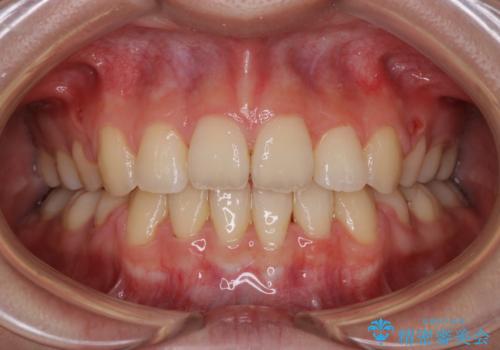

唇を閉じやすく 出っ歯の抜歯矯正

担当医 藤巻太一朗